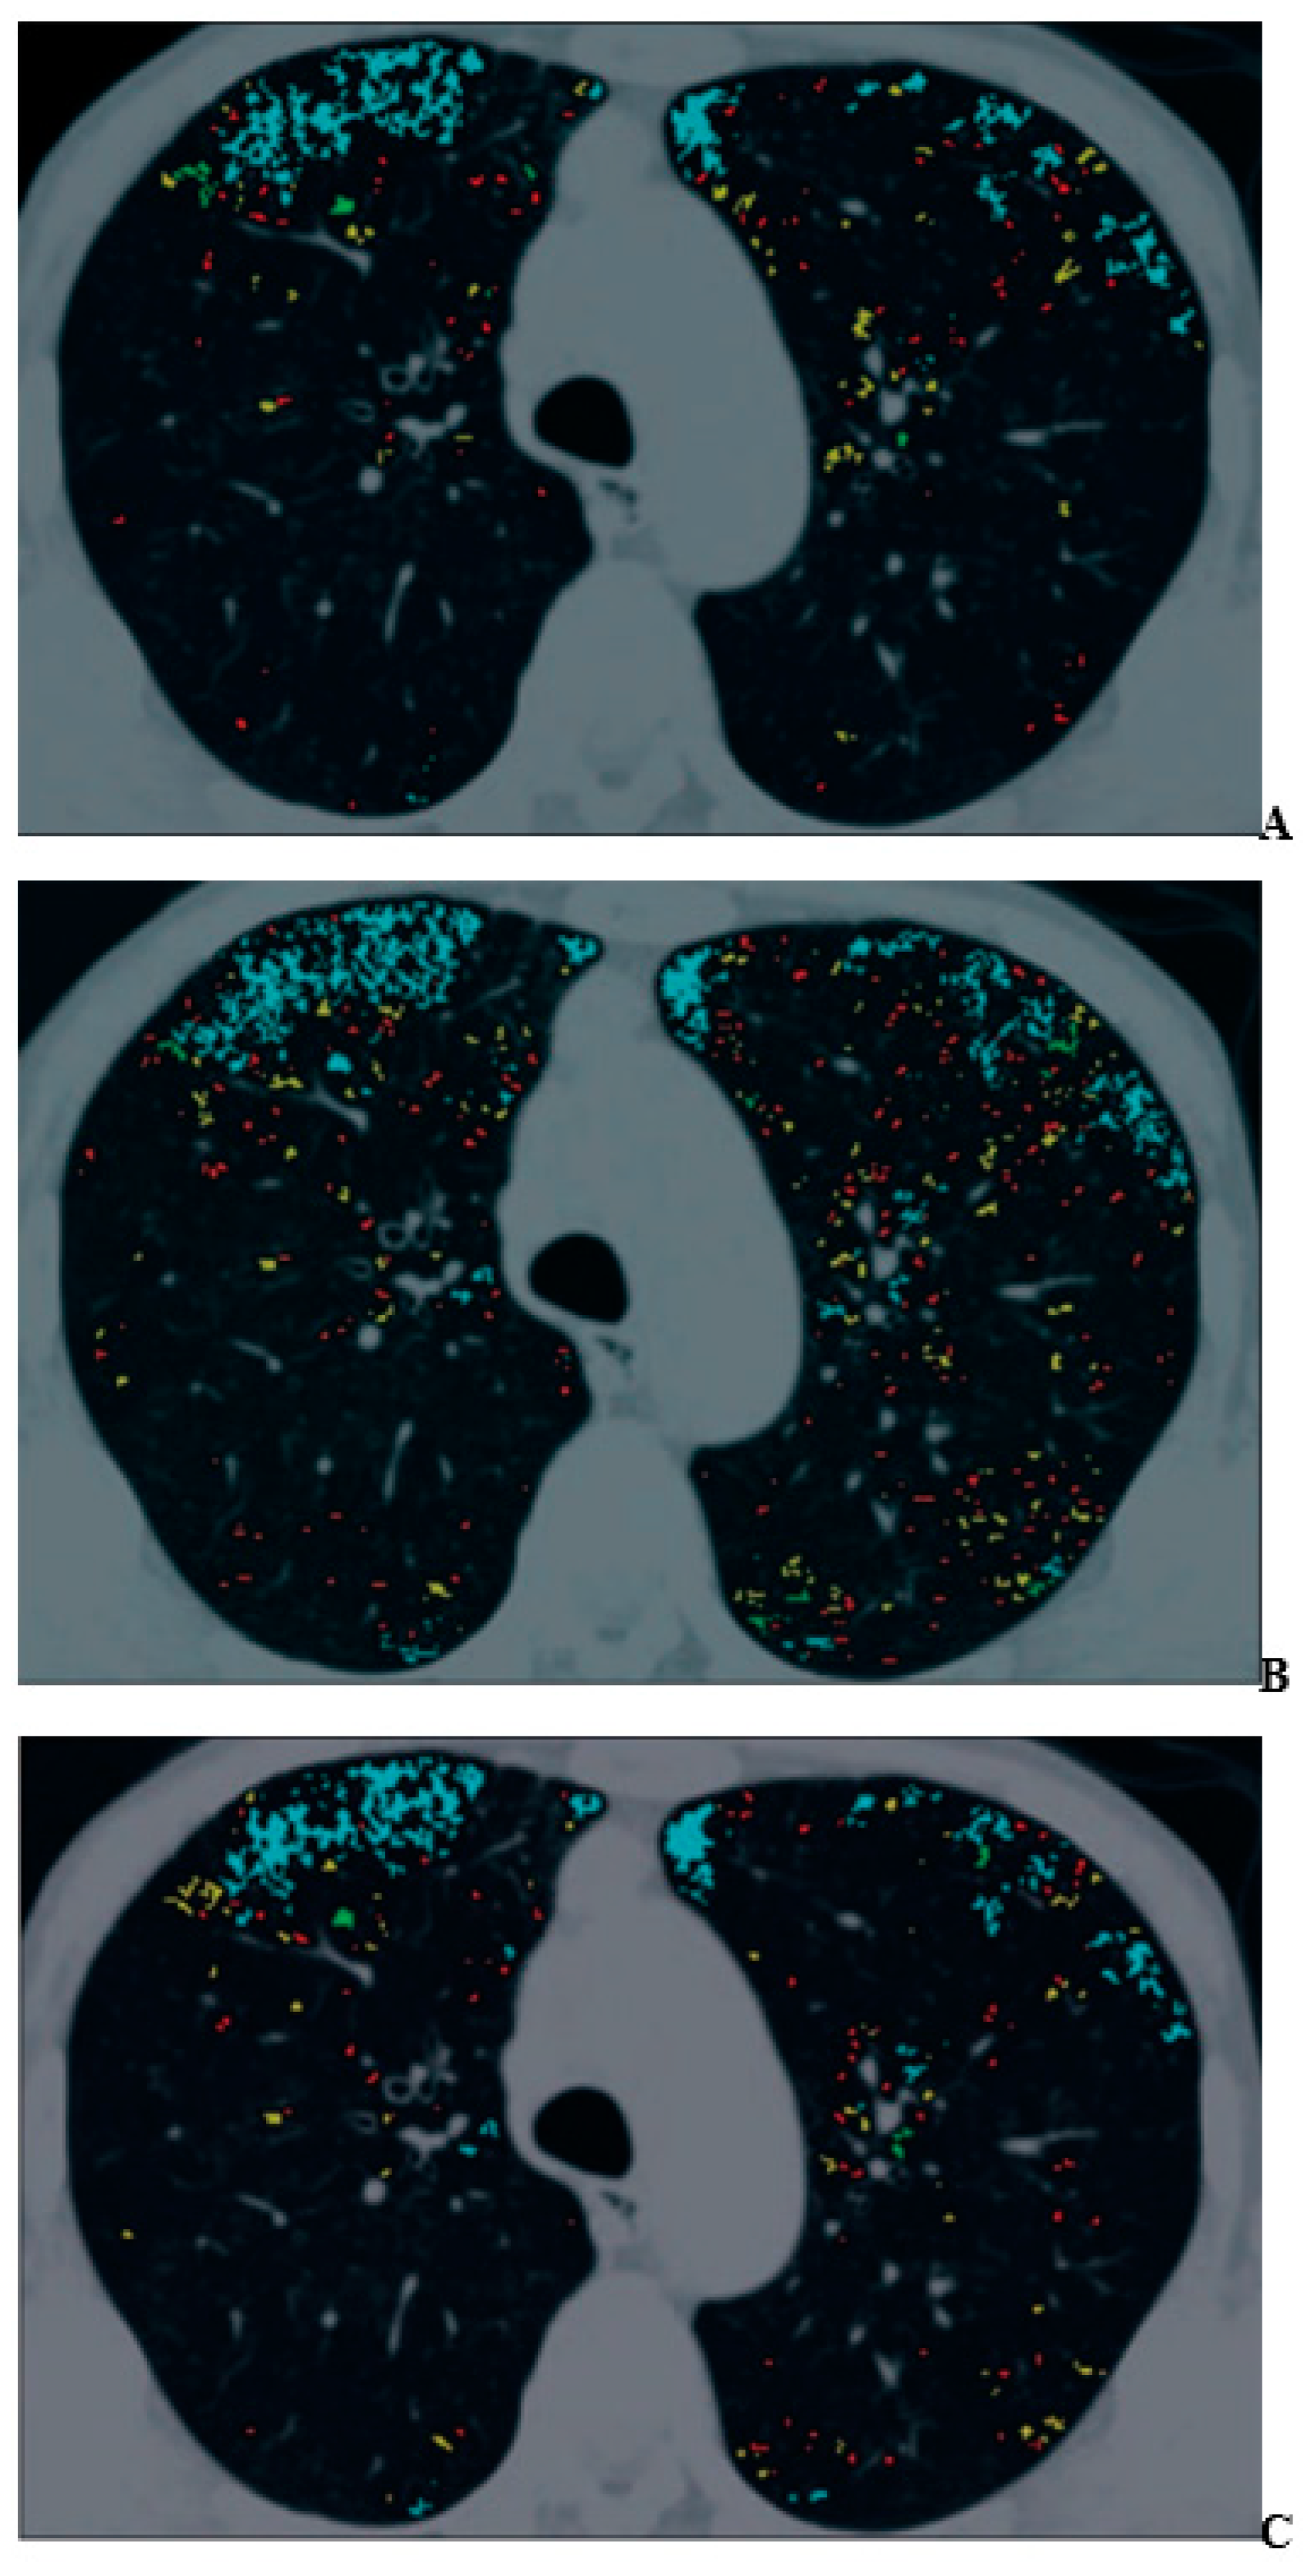

For COPD assessments, CT can be used to assess morphological and functional changes related to COPD [48,49,50,51,52,53,54,55,56,57,58,59,60]. During the last few decades, many commercially available and proprietary software products as well as various visual scoring systems have been used for the CT-based assessment of COPD, with two major approaches reported in the literature for quantitative CT assessment of COPD [48,49,50,51,52,53,54,55,56,57,58,59,60]. One is the determination of the percentage of low attenuation area (%LAA) in the lung, which indicates emphysema changes, and the other is the determination of the wall area ratio (WA%) of the bronchi, which indicates bronchial lumen narrowing and bronchial wall thickening [48,49,50,51,52,53,54,55,56,57,58,59,60]. In the past literature [48,49,50,51,52,53,54,55,56,57,58,59,60], it has been suggested that the %LAA has a good correlation with FEV1/FVC, %FEV1, %DLCO, or DLCO/VA and that the WA% also has a good correlation with FEV1/FVC and %FEV1. Therefore, it is suggested that these imaging parameters are useful as quantitative imaging biomarkers for COPD [48,49,50,51,52,53,54,55,56,57,58,59,60]. In addition, three-dimensional (3D) airway luminal volumetry has been introduced as another quantitative method for evaluating the airways of COPD patients [58,59]. Taking the findings provided by these quantitative CT assessments of COPD and the need for radiation dose reduction strategies into consideration [42,43,44,45,46,58,59,60], the application of IR algorithms has been considered an important issue for an accurate quantitative CT evaluation of COPD. One study demonstrated that agreement for the %LAA between standard-dose CT obtained at 300 mA and reduced-dose CT at 50 mA tended to improve when using AIDR 3D rather than conventionally applied FBP [44] (Figure 1).

Figure 1.

A 70-year-old man with mild pulmonary emphysema (permission from reference [44]). (A–C) Images show low-attenuation lung regions with standard-dose CT (A), low-dose CT without adaptive iterative dose reduction using 3D processing (B), and low-dose CT with adaptive iterative dose reduction using 3D processing (C). Color coding of low-attenuation lung regions is as follows: class 1, red; class 2, yellow; class 3, green; and class 4, cyan.